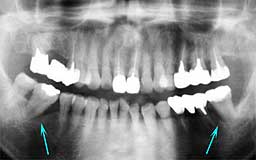

★ Oさん 61歳

Oさんもそんななかのひとりです。来院直後の6年間にブランクがあって、その時失った下

顎の前歯部を除けばかなりの状態をキープしているといえます。61歳としては余りにも条

件が良すぎたためにメインテナンスを積極的に勧めなかったことが少し悔やまれます。

| Oさん 初診時 61歳 男性 上顎臼歯部に中程度以上の歯槽骨破壊が認められるが残存する歯の数は多い |

Oさん 20年後 81歳歳 補綴(ほてつ)物が多いことに不満を感じるが親知らずを含む残存歯数27本は立派 |